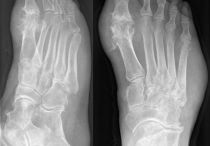

Кисть – это одна из самых функционально сложных частей тела. Ее особенностью является то, что она состоит из большого количества мелких костей и предназначается для выполнения тонких манипуляций. Обычно боль в кистях рук появляется после серьезной нагрузки, вследствие перелома, продолжительной работы за клавиатурой компьютера, растяжения. При этом болевые ощущения могут быть настолько сильными, что лишают человека возможности работать руками. Он даже не всегда может обслужить себя. Медлить с лечением такой боли не стоит, так как можно остаться инвалидом.